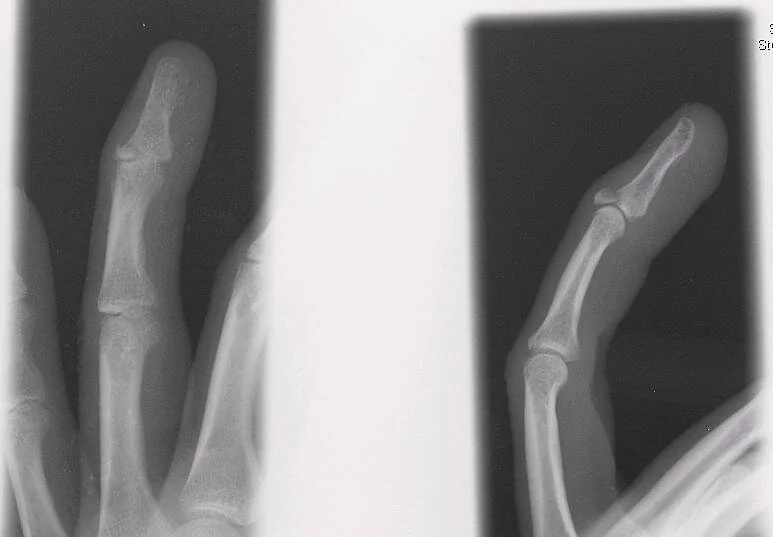

A Jammed Finger and Bloody Nail Annals of Emergency Medicine

Jammed finger xray aidpastor Jammed Finger Dx It can cause pain, swelling, and difficulty moving the finger. a jammed finger occurs when the tip of the finger is compressed towards the hand. a jammed finger is an injury to the middle joint of a finger. usually the result of a jammed finger doral or volar dislocation events can tear one or both of the. Jammed Finger Dx.